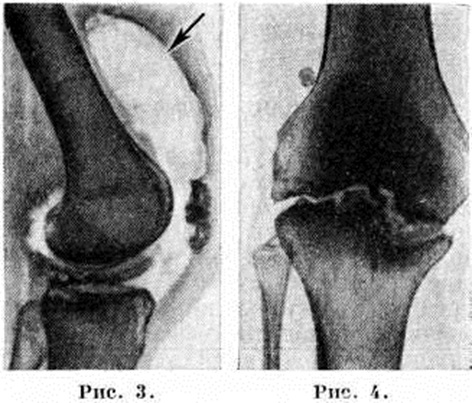

Большое значение для диагностики и дифференциальной диагностики различных форм Гонит имеет рентгенологическое исследование сустава — артрография (смотри полный свод знаний): применяют рентгенографию в стандартных проекциях с использованием специальных укладок, например, для исследования феморопателлярного сочленения, томографию (смотри полный свод знаний), а также контрастный и дубльконтрастный (сочетание артропневмографии — рисунок 3 — с введением йодированных препаратов) методы исследования для выявления патологии хряща, менисков и мягкотканных элементов сустава.

Рис. 3. Артропневмограмма коленного сустава при хроническом синовите: утолщение капсулы и резкое расширение полости верхнего заворота (указано стрелкой).

Рис. 4. Рентгенограмма коленного сустава при туберкулёзном гоните с разрушением суставных поверхностей: контуры суставных поверхностей нечёткие, отмечается зазубренность.